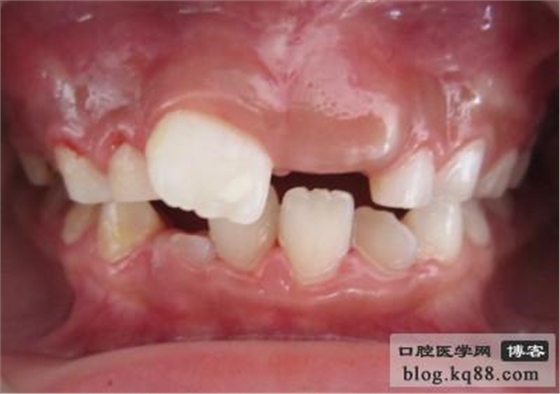

齦瓣切除助萌術(shù)前